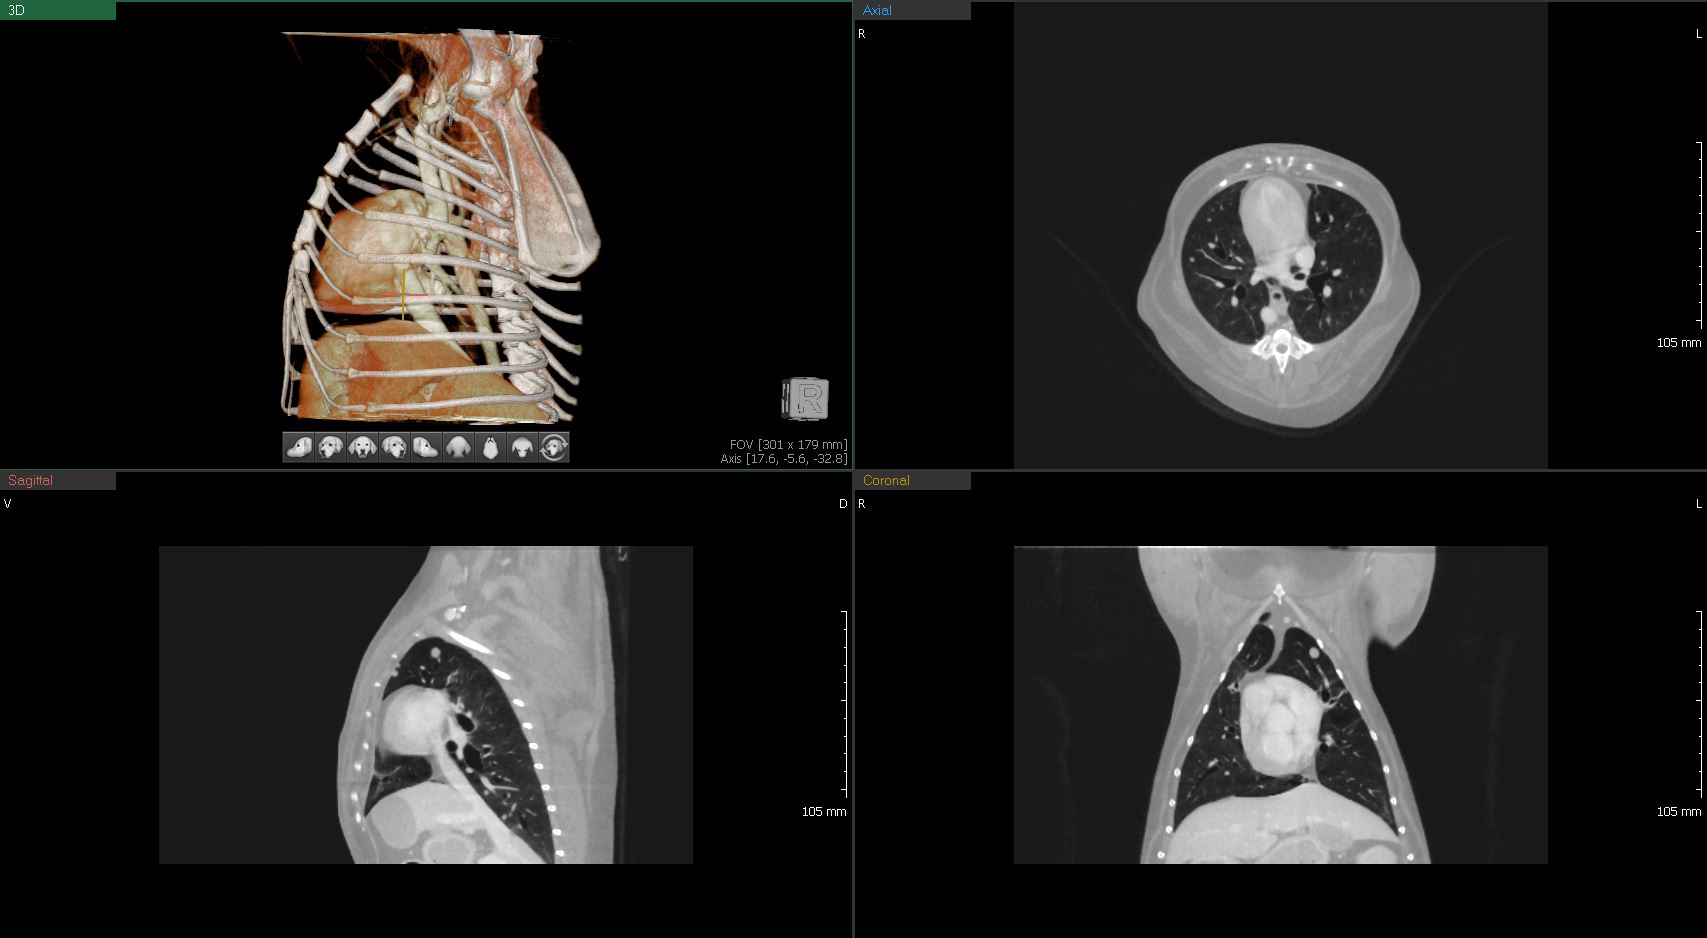

CT

연산동물의료센터의 CT검사는 짧은 촬영으로도

정밀한 3D 입체영상을 얻을 수 있습니다.

흉부심장 및 대형 혈관, 폐 실질 및 기관, 기관지

흉부 CT

흉부